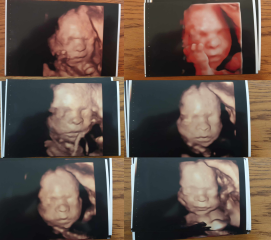

SpicyMoth · 16/05/2024 21:59

My DM (who is positively losing her mind with excitement over her first grandchild) gifted us a private 3D scan today at 24 +2.

He's still got some baby fat to put on, but all in all - I think he's rather cute if I do say so myself - Even with the slight janky-ness that comes with a 3D scan!

We got a super cute few seconds long clip of him having a good yawn in there too, which I adore - He's also definitely a thumb sucker already (Just like I was! God I hope that doesn't become a habit for him to have to kick >.<).

He's coming in at 1lb 11oz as of today, I'm 4ft11 and my DH is 6ft2, so I'm expecting this baby may well end up being absolutely huge in 3 months time - I pray he doesn't tear me asunder! ๐Ÿ˜…๐Ÿ˜ฌ

Honestly I really would highly recommend it, the whole experience was lovely and they gave me a USB with loads of video and loads of extra pictures as well as the printed out ones I posted above - They also let you have more than just one other person in the room so my DH, my mum and my step-dad-to-be all got to come in and see the little man too so if you have any other family members who'd love to come in and see the live scan, it's 100% worth it imo!

What beautiful photos @SpicyMoth 3d scans are absolutely magical and what a lovely keepsake. We had one at 25 weeks with DD and we still look at it now 8 years on. Unfortunately I donโ€™t think weโ€™ll have one this time due to the amount of extra growth scans Iโ€™m having.